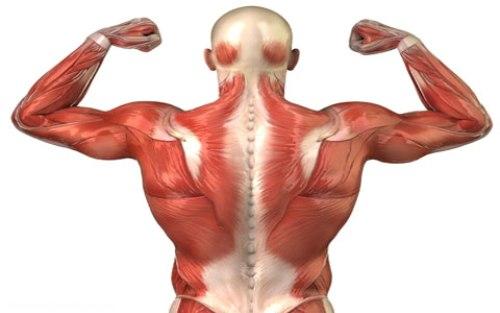

عضلات پشت جزو عضلات خلفی تنه محسوب می شوند و شامل ۸ عضله ذوزنقه، پشتی بزرگ، متوازی الاضلاع، گوشه ای، دندانه ای خلفی فوقانی، دندانه ای خلفی تحتانی، پشتی دراز و مربع کمری می باشد. هر کدام از این عضلات به ترتیب توضیح داده می شوند.

عضله ذوزنقه

این عضله پهن و حجیم سطح زیادی از پشت را می پوشاند. با توجه به وسعت و حجمی که دارد اعمال زیادی را نیز عهده دار است. به همین علت قسمت های مختلفی در عضله قابل تشخیص هستند.

عضله پشتی بزرگ

این عضله نیز از عضلات بزرگ پشت بوده و سطح وسیعی را می پوشاند. قسمت فوقانی این عضله توسط قسمت تحتانی عضله ذوزنقه پوشانده می شود. عضله پشتی بزرگ از روی خارهای شش مهره تحتانی پشتی و تمام مهره های کمری و سطح خلفی خاجی و قسمت خلفی تاج خاصره در هر طرف، زاویه تحتانی کتف و سه یا چهار دنده تحتانی، شروع می شود. تارهای عضله به طرف فوقانی و خارج کشیده شده و به وسیله یک تاندون بلند به قسمت قدامی استخوان بازو ( انتهای تحتانی ناودان دوسری) چسبندگی پیدا می کنند.

عضله متوازی الاضلاع

این عضله در اصل دو عضله است که شباهت زیادی در نحوه قرار گیری و عمل دارند. عضله متوازی الاضلاع بزرگ از روی خارهای مهره های دوم تا پنجم پشتی شروع می شود و به بخش تحتانی لبه داخلی استخوان کتف متصل می شود. جهت کشیدگی تارهای این عضله مایل است. عضله متوازی الاضلاع کوچک نیز از روی انتهای تحتانی رباط نوکه در پشت گردن و خارهای مهره های هفتم گردن و اول پشتی شروع شده و به ریشه خار استخوان کتف متصل می شود، تارهای این دو عضله به موازات هم قرار دارند.

عضله گوشه ای

تارهای این عضله از روی زوائد عرضی چهار مهره اول گرد به پایین و خارج کشیده شده و به قسمت فوقانی لبه داخلی استخوان کتف بین زوایه فوقانی و ریشه خار کتف چسبندگی پیدا می کنند.

عضله پشتی دراز

عضله ای طویل است که از استخوان پس سری تا خاجی کشیده می شود. این عضله از روی استخوان خاجی، زوائد خلفی مهره های کمری، تاج خاصره شروع شده و با توجه به محل چسبندگی انتهای دیگر تارها به سه گروه عضلانی تقسیم می گردد:

۱- خاصره ای، که روی دنده ها کشیده می شود.

۲- طویل، که روی زوائد عرضی مهره ها کشیده می شود.

۳- شوکی که روی زوائد شوکی مهرها کشیده می شود.

عضله مربع کمری

عضله ای پهن است که در دو طرف ستون فقرات در ناحیه کمر قرار دارد. این عضله از روی بخش خلفی تاج خاصره شروع شده و با چسبندگی روی زوائد عرضی مهره های اول تا چهارم کمر روی لبه تحتانی دنده دوازدهم متصل می گردد.